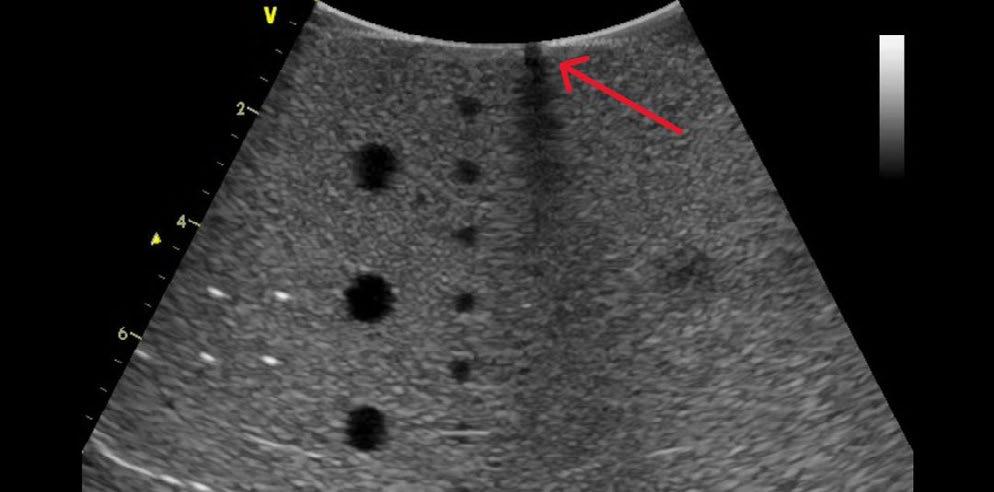

WHAT IS IMAGE DROPOUT?

Image dropout is just that…A section of the image that has no information or that has “dropped out” (technically called hypoechoic). Typically, this appears as a black vertical line or shadowy region of the image. Because the acoustic elements are not pulsing (or not working as expected), no information (or erroneous information) is provided to the scanner for display.

Image Dropout

Well, the term artifact refers to any unwanted and unexpected anomaly in an image. Typically, color artifacts appear as unwanted flashes, vertical streaks, or areas of non-descript color variations in the image. Take a look at the photos.